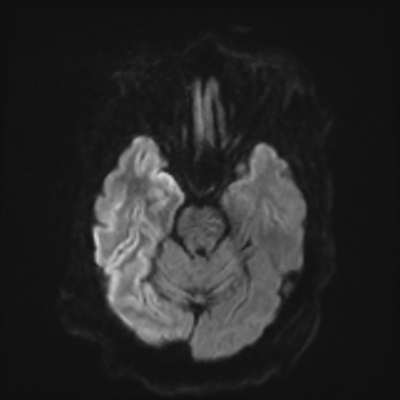

You come back the next day and see how things are going. The patient's electrographic record has shown a moderate encephalopathy (diffuse slowing, disorganization) with frequent right posterior quadrant delta slowing. Based on this result, and an adequately improved clinical examination, you give the okay to proceed with obtaining an MRI of his brain. This is shown below.

MRI brain (DWI)